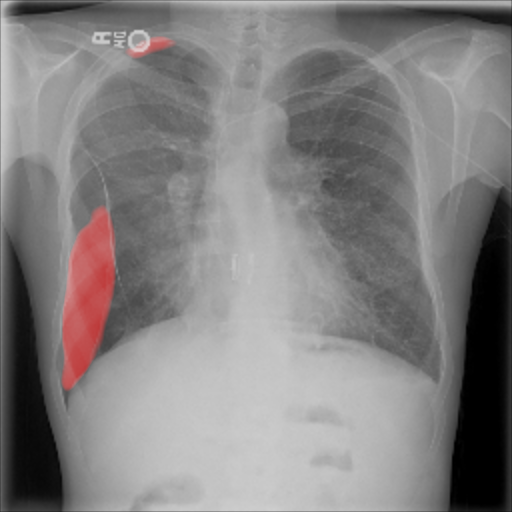

As pixel-level ground truth annotations were available only for a subset of the images, 871 images in total were used for training the FCN for 400 epochs. As a loss function, a weighted cross entropy (25.0 for pneumothorax pixels and 0.5 for non-pneumothorax pixels in order to account for the smaller size of pneumothorax regions) was employed at pixel-level with an initial LR of . With an average AUC of 0.920.02, the overall performance of this method is worse than the CNN and MIL. On the other hand, the FCN generates pixel-level probabilities (cf. Fig. 5(d)), which indicate the location of the pneumothorax. The average Dice coefficient for positively classified cases is .